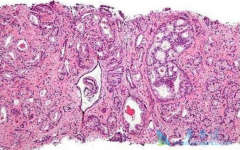

据相关的数据统计, 前列腺癌 在我国的发病率呈现不断上升的趋势,年增长速度已经超过了5%,位居所有肿瘤增长率的前两位。根据前列腺癌的不同分期,患者的治疗方式和预后也有所不同。精准判断前列腺癌的分期,可以帮助专业的医生来确定癌肿的范围和活性 ...

对于前列腺癌患者,定期筛查肿瘤标志物可在疾病的早期发现存在的风险因素。若在体检的无症状人群中发现可疑者,通过风险因素评估,确定高危人群后,再及时展开进一步检查和治疗,可有效降低患者死亡率。血清前列腺特异性抗原(PSA)是前列腺癌重要且敏感 ...